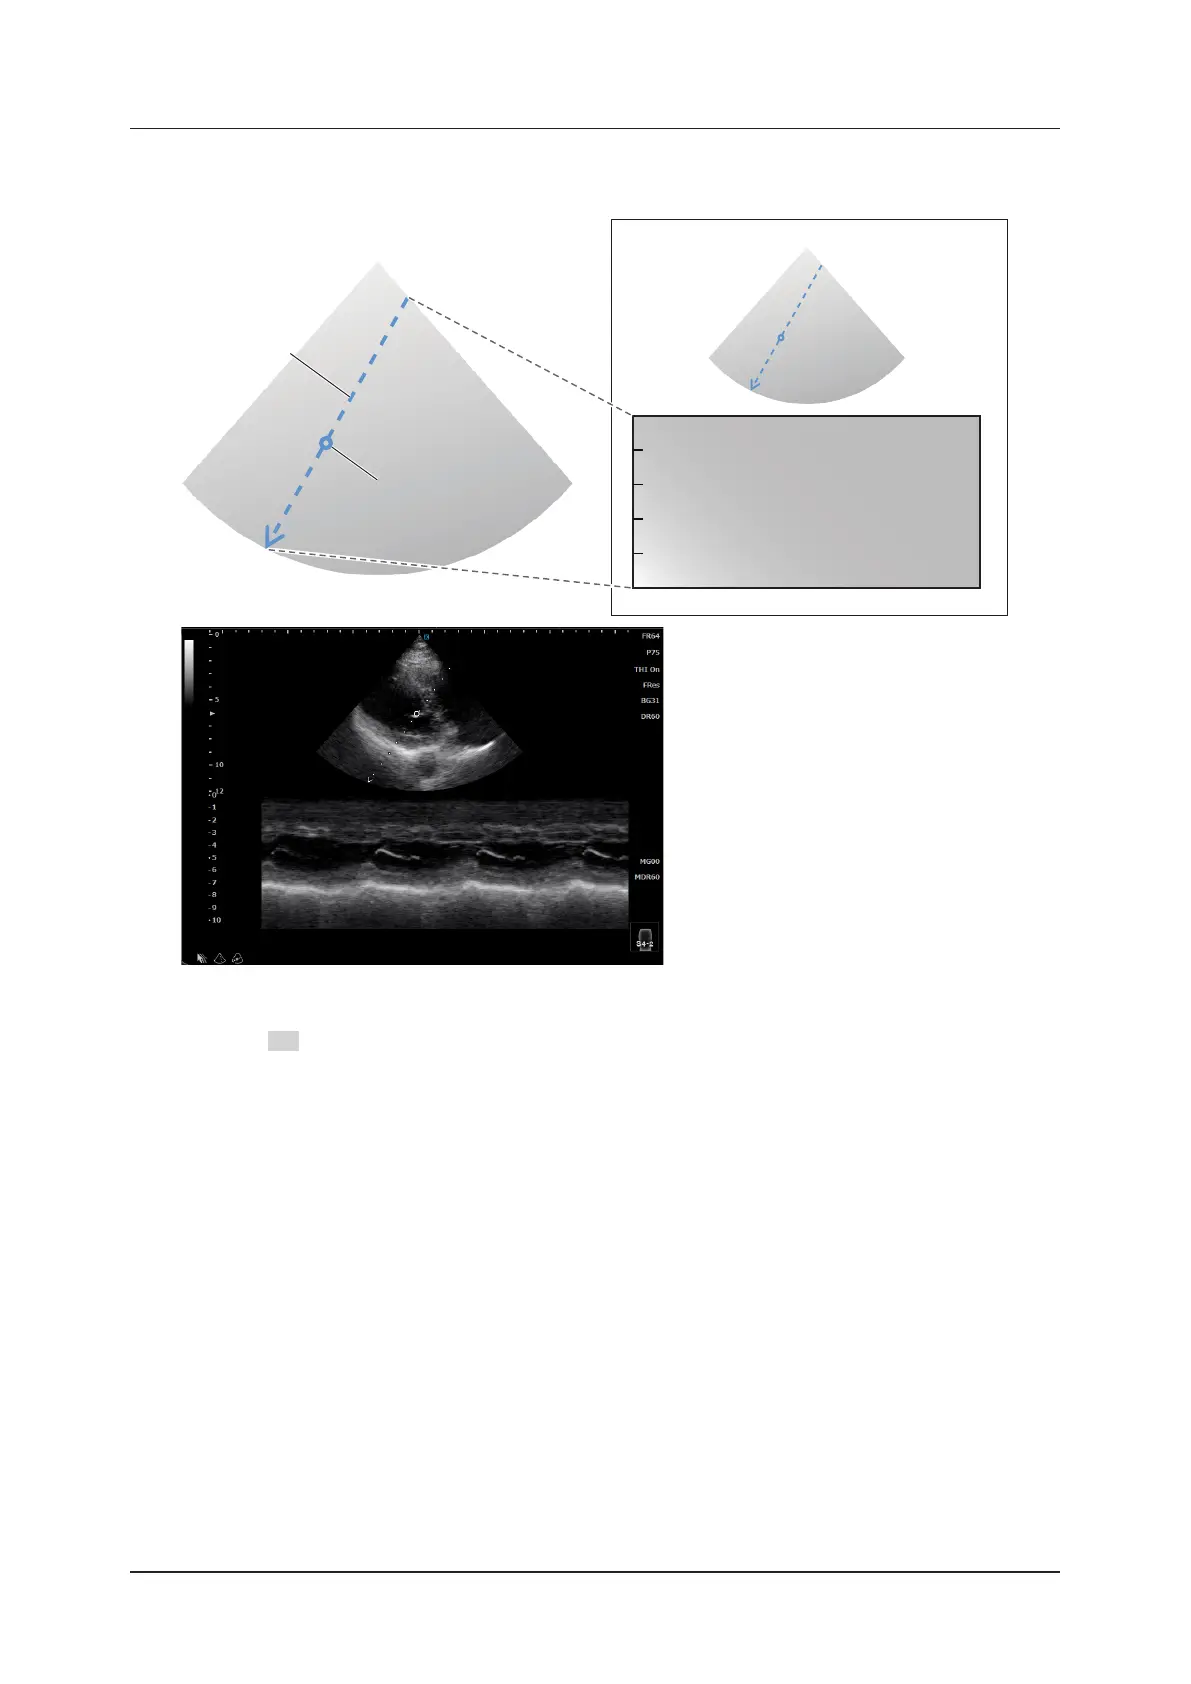

When [Ana-M] is set to [On], the freely movable Ana-M cursor and the rotation center cursor

appear.

Ana-M cursor

Rotation center cursor

<Anatomical M image>

The Ana-M cursor can be rotated centered on the rotation center cursor by the Angle operation (the item in the M-

mode menu or F2 Rotate).

The Ana-M cursor is displayed as a straight line from one side to another side of the B image. Among the intersec-

tions of the line (cursor) with the sides, the one corresponding to the end position of the M image is displayed as

an arrow. Among the intersections, the one always having a deeper display depth for the B image is the end posi-

tion side. (When the cursor’s rotation angle is 180 degrees and horizontal to the B image, the start and end posi-

tions depend on the setting of the B-mode parameter, [LR Flip]. When [LR Flip] is set to [Left], the left side is the

start position and the right side is the end position.)

The rotation center cursor is displayed at the center of the Ana-M cursor. It can be moved with trackball or touch

operation.